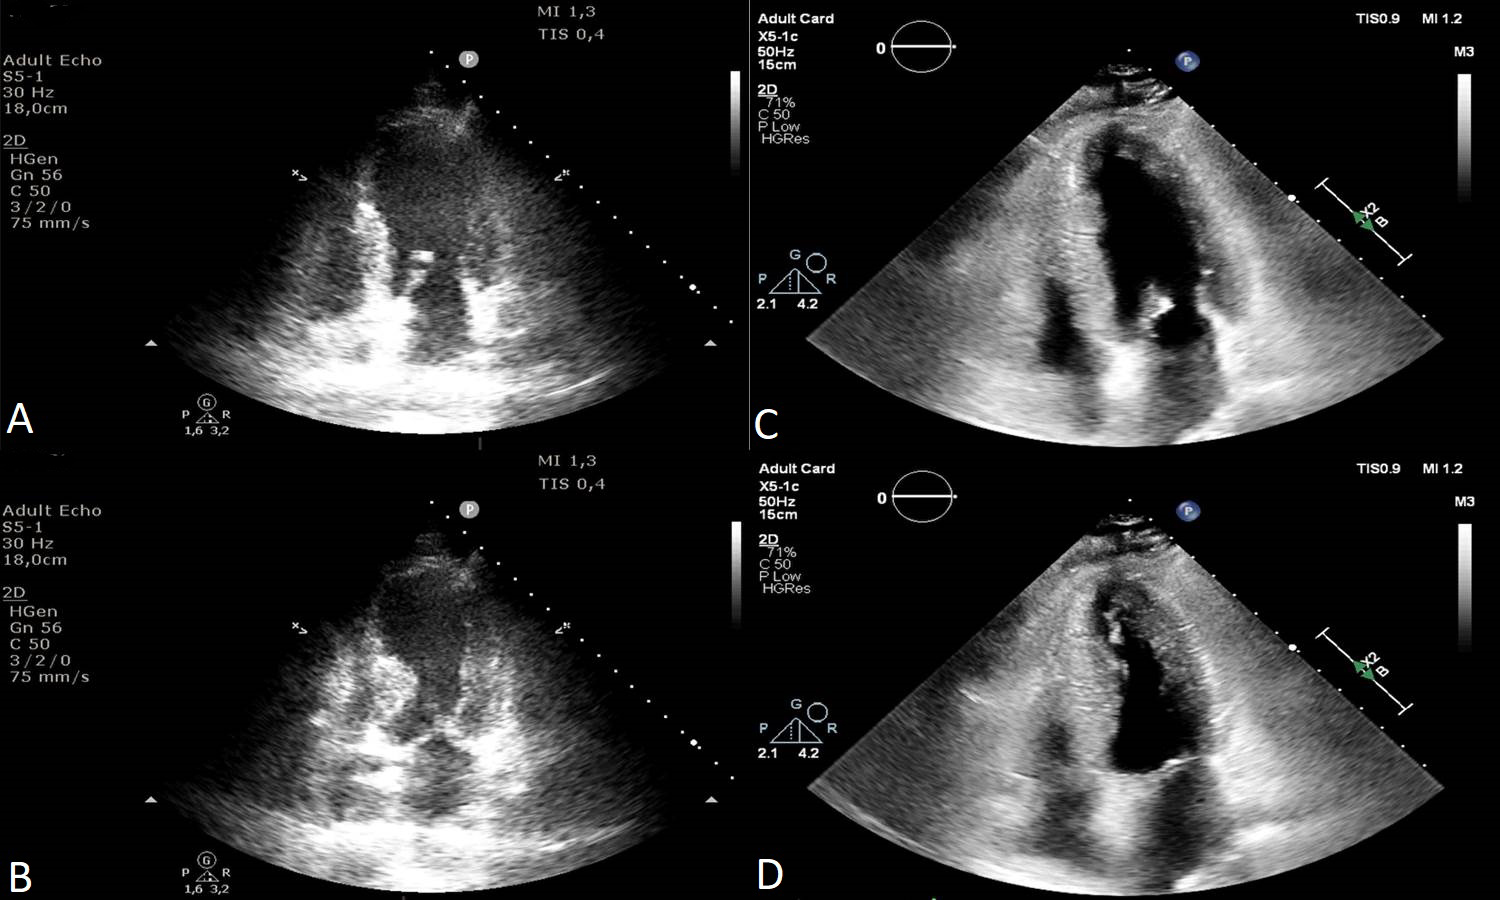

CMR using T2 weighted images is a noninvasive alternative in discovering myocardial edema. The areas of myocardial edema correlated with RWMA areas [107, 108] (Fig. 5). Studies who performed endomyocardial biopsies in Takotsubo patients proved there is inflammation in the motion abnormalities areas [109].

Fig. 5.Cardiac Magnetic Resonance Imaging of a 78 years old female patient in the acute phase of Takotsubo Syndrome. Myocardial edema can be observed in the apical regions of the left ventricle in T2 weighted images (A and B) and the lack of late gadolinium enhancement in C and D.

Generally, there is no fibrosis detected on late gadolinium enhancement (LGE) CMR. In the chronic phase, CMR follow up reveals normal ventricular function, normal regional wall motion, no edema, no necrosis and no fibrosis [110]. Even though in most Takotsubo cases there was no LGE present, LGE positive cardiac magnetic Resonance imaging (MRI) in TS were reported in a few cases [111, 112, 113]. A two-step recovery in the LV function in TS was described. The first step was the recovery of the LV systolic function and the latter one was the improvement of the diastolic one, assessed by LV peak filling rates and left atrial filling volumes [114]. CMR based strain analysis of the LV in the acute phase revealed that CMR does have prognostic value in TS patients. However, prognosis was mainly influenced by the patients’ comorbidities [115].